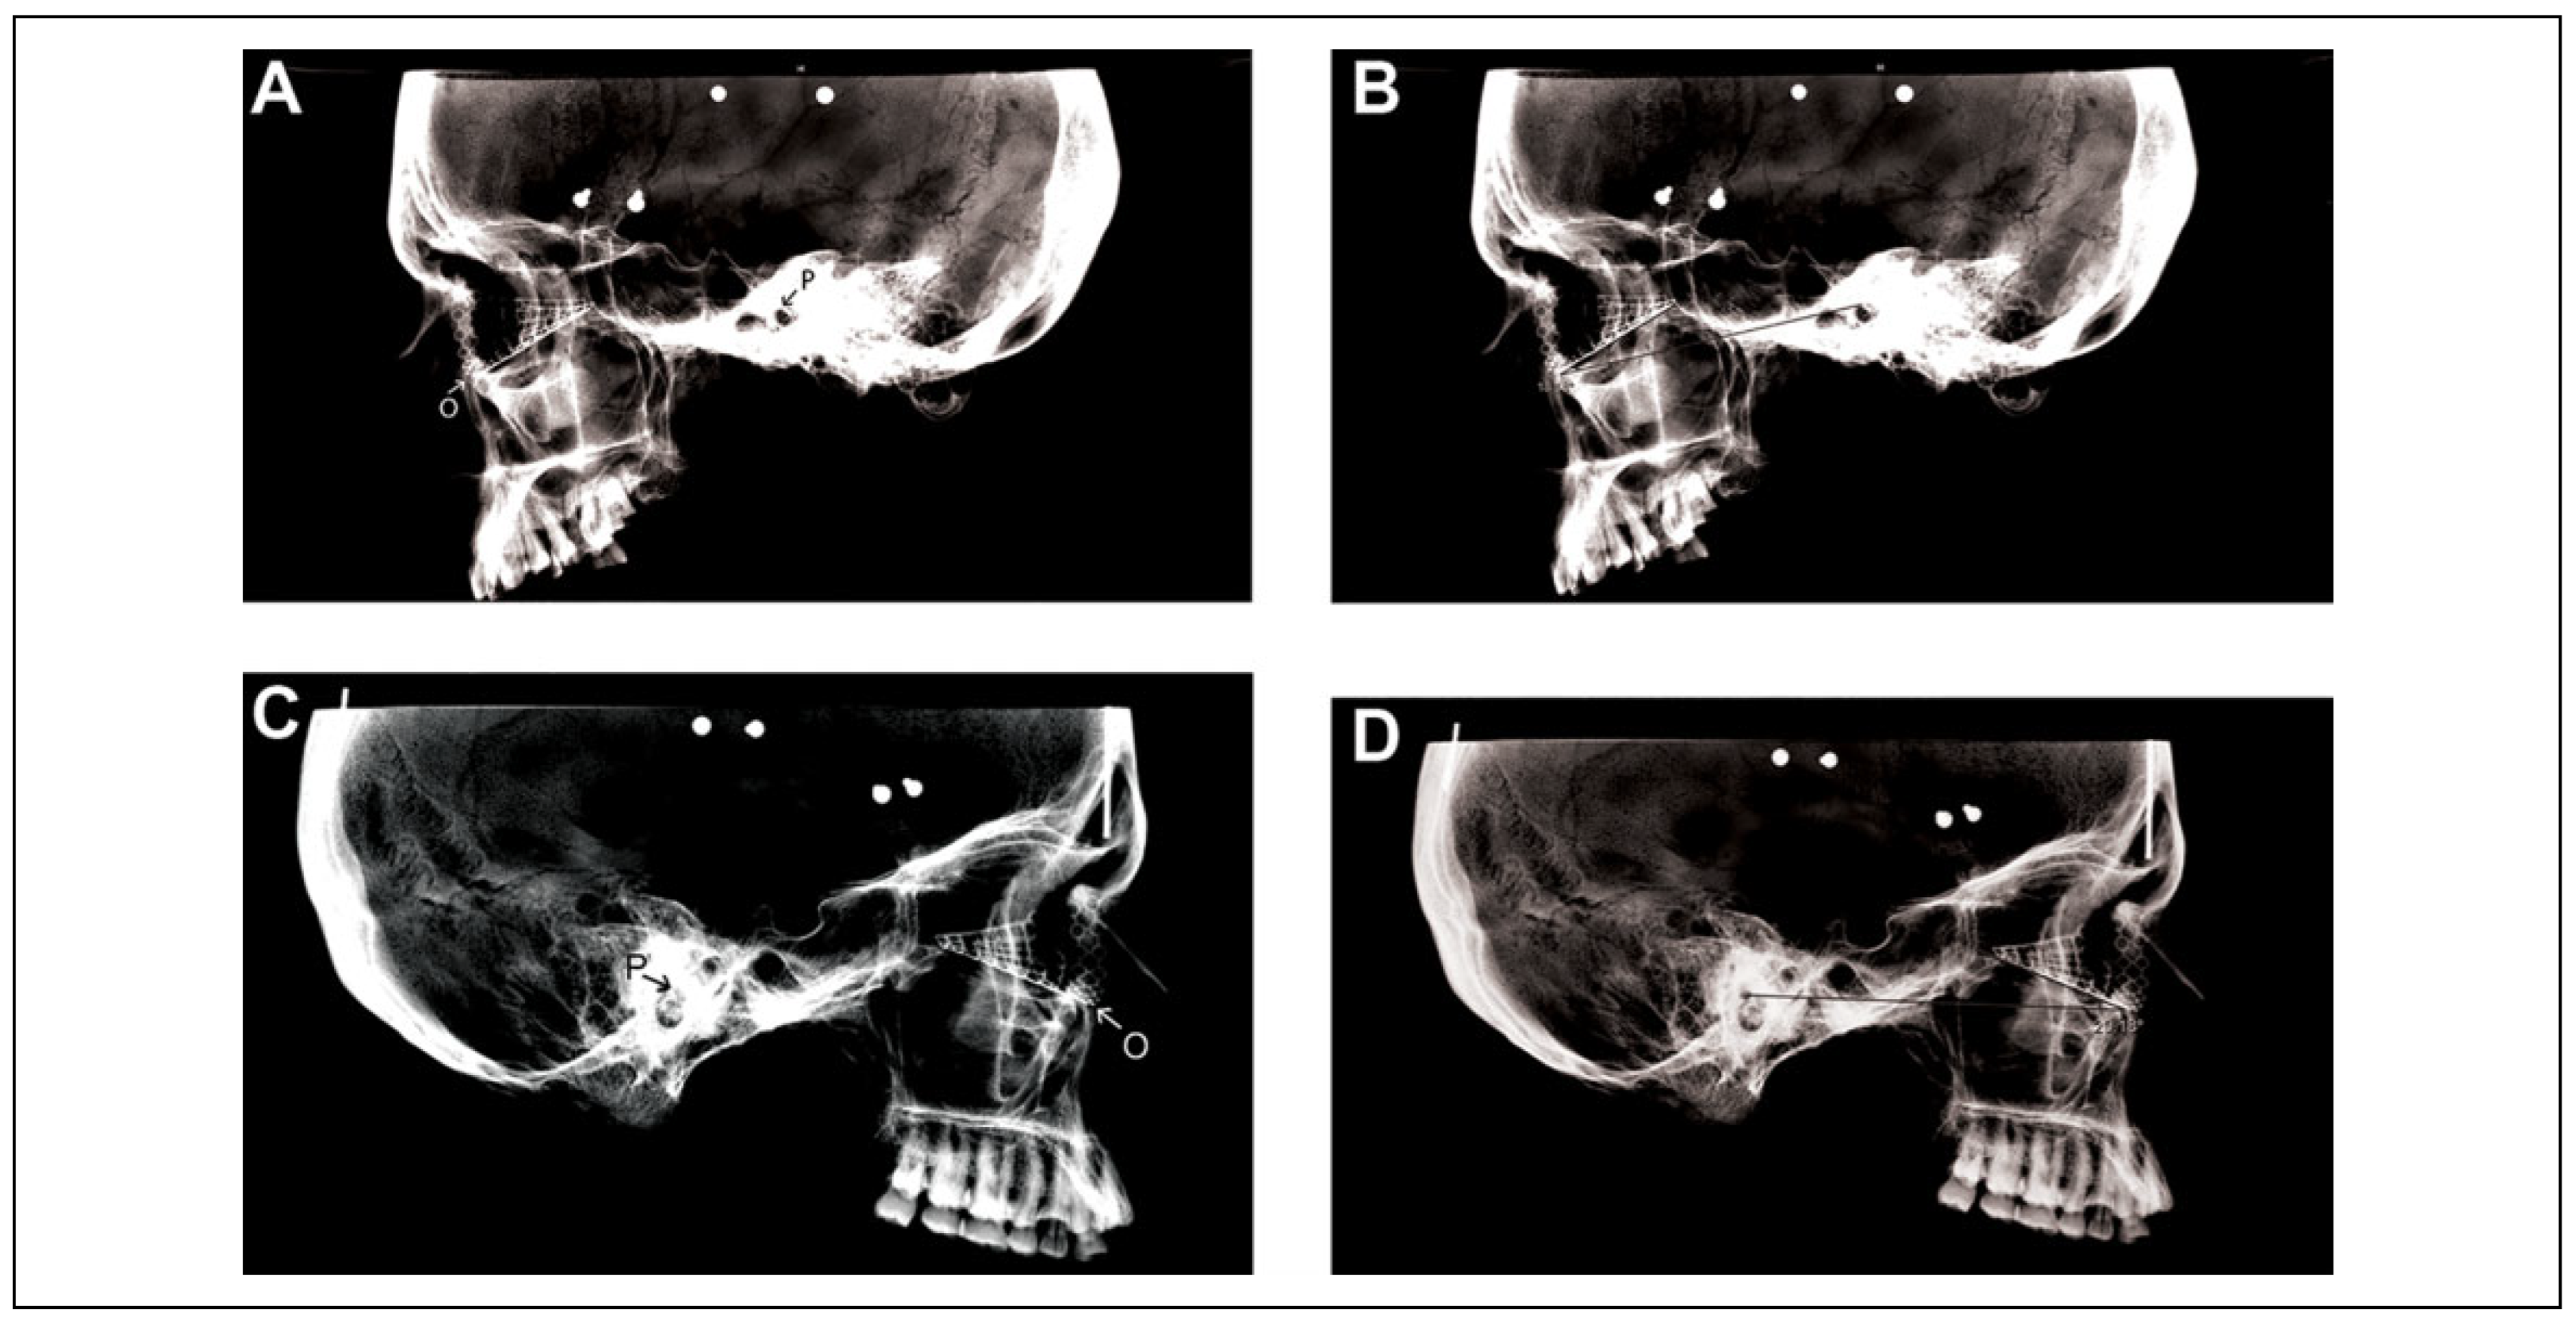

Titanium fan plate implants (Figure 1) by DePuy Synthes Companies (West Chester, Pennsylvania) were molded and affixed with masking tape to individual orbits on each side separately. Next, flat plate lateral radiographs were obtained for each orbit containing an implant (Figure 2). The radiography flat plate was placed on the side where the implant was placed in order to minimize the beam magnification effect. We were careful to obtain as true a lateral image as possible. The implants, though not trimmed, were seated well into each orbit, from the inferior orbital rim to the site where a posterior ledge would be encountered in a true fracture. None of these skulls had orbital floor fractures. Therefore, no distortion was expected in the way the implant was placed in each orbit. In order to make the specimens easier to handle during imaging, we had removed the mandibles.

All radiographs were uploaded on the Merge picture archiving and communication system platform (Watson Health Imaging, Chicago, Illinois), and this software was used to obtain the angle that the trough of the implant, on lateral view, made with the Frankfort horizontal plane (Figure 2).

Figure 2. (A,C) Examples of specimens with left and right orbital floor implants; labeled porion (P) and orbitale (O). (B,D) Angle, 18° and 20°, measured between the trough of the implant and the Frankfort horizontal plane, extending from porion to orbitale.

The mean angle that the trough of the implant made with the Frankfort horizontal plane was 20.1 ± 2.4° (standard deviation) in the male specimens (95% confidence interval [CI], 18.8-21.5°) and 22.6 ± 2.0° in the female specimens (95% CI, 21.4-23.7°). On any given skull, we noted occasional differences between the right and left orbits, but overall, such differences were negligible. A statistical analysis demonstrated no statistically significant differences between this angle of inclination in male and female specimens (P value = 0.62). For the combined specimens (ie, 28 sides in 14 skulls), the overall mean angle was 21.4 ± 2.5° (95% CI, 20.4-22.3°). Our data are summarized in Table 1.

Measurement of the AP angle of inclination that a well-placed orbital implant makes relative to the Frankfort horizontal plane can be used to provide useful clinical information. Technically, this angle can be measured between the line that the trough of the implant makes with the Frankfort horizontal plane on a lateral plain radiograph. This study aims to define an average value for this angle of inclination that would be instrumental for the surgeon intraoperatively in gaining a better understanding of the position of the orbital implant. In our study of 14 skull specimens, we demonstrate this angle to be 21.4 ± 2.5°. Information regarding the AP inclination angles of the orbital floor has not been widely presented in the anatomic, surgical, or radiologic literature to date, which makes this study unique in presenting a clinically relevant value for this angle—a value based on how the implant sits in the orbit.